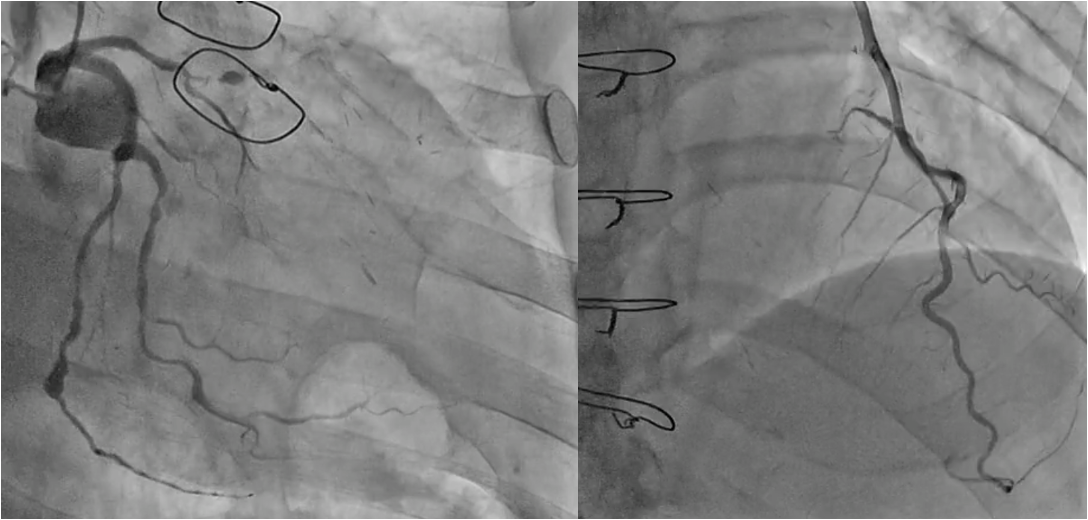

RCA: Seg1)total occlusion, Bypass graft SVG-RCA 99%. LCA:LAD Seg7)total occlusion,LCx Seg12)90%,seg13)90%.seg14)total occlusion, Bypass graft LITA-LAD・FreeRITA-LCX patent, SVG-seg9)occluded.

PCI for the degenerated SVG was determined to be at high risk of distal embolism so we planned to perform PCI for native RCA. Antegrade wire crossing was thought to be difficult (J-CTO score was 3 : calcification, bending and lesion length), therefore we planned retrograde approach via SVG. To avoid ischemia during the retrograde procedure, we dilated the severe stenotic lesion in SVG with small balloon and then micro catheter was advanced. It was very difficult to pass the graft anastomosis, but reverse wire technique at distal RCA was effective. Even after the advancement of both antegrade and retrograde wires, it was also difficult to pass the CTO lesion due to strong bending. Finally, retrograde wire was passed with Reverse CART technique and externalization was achieved. After DES implantation, native RCA was nicely revascularized.